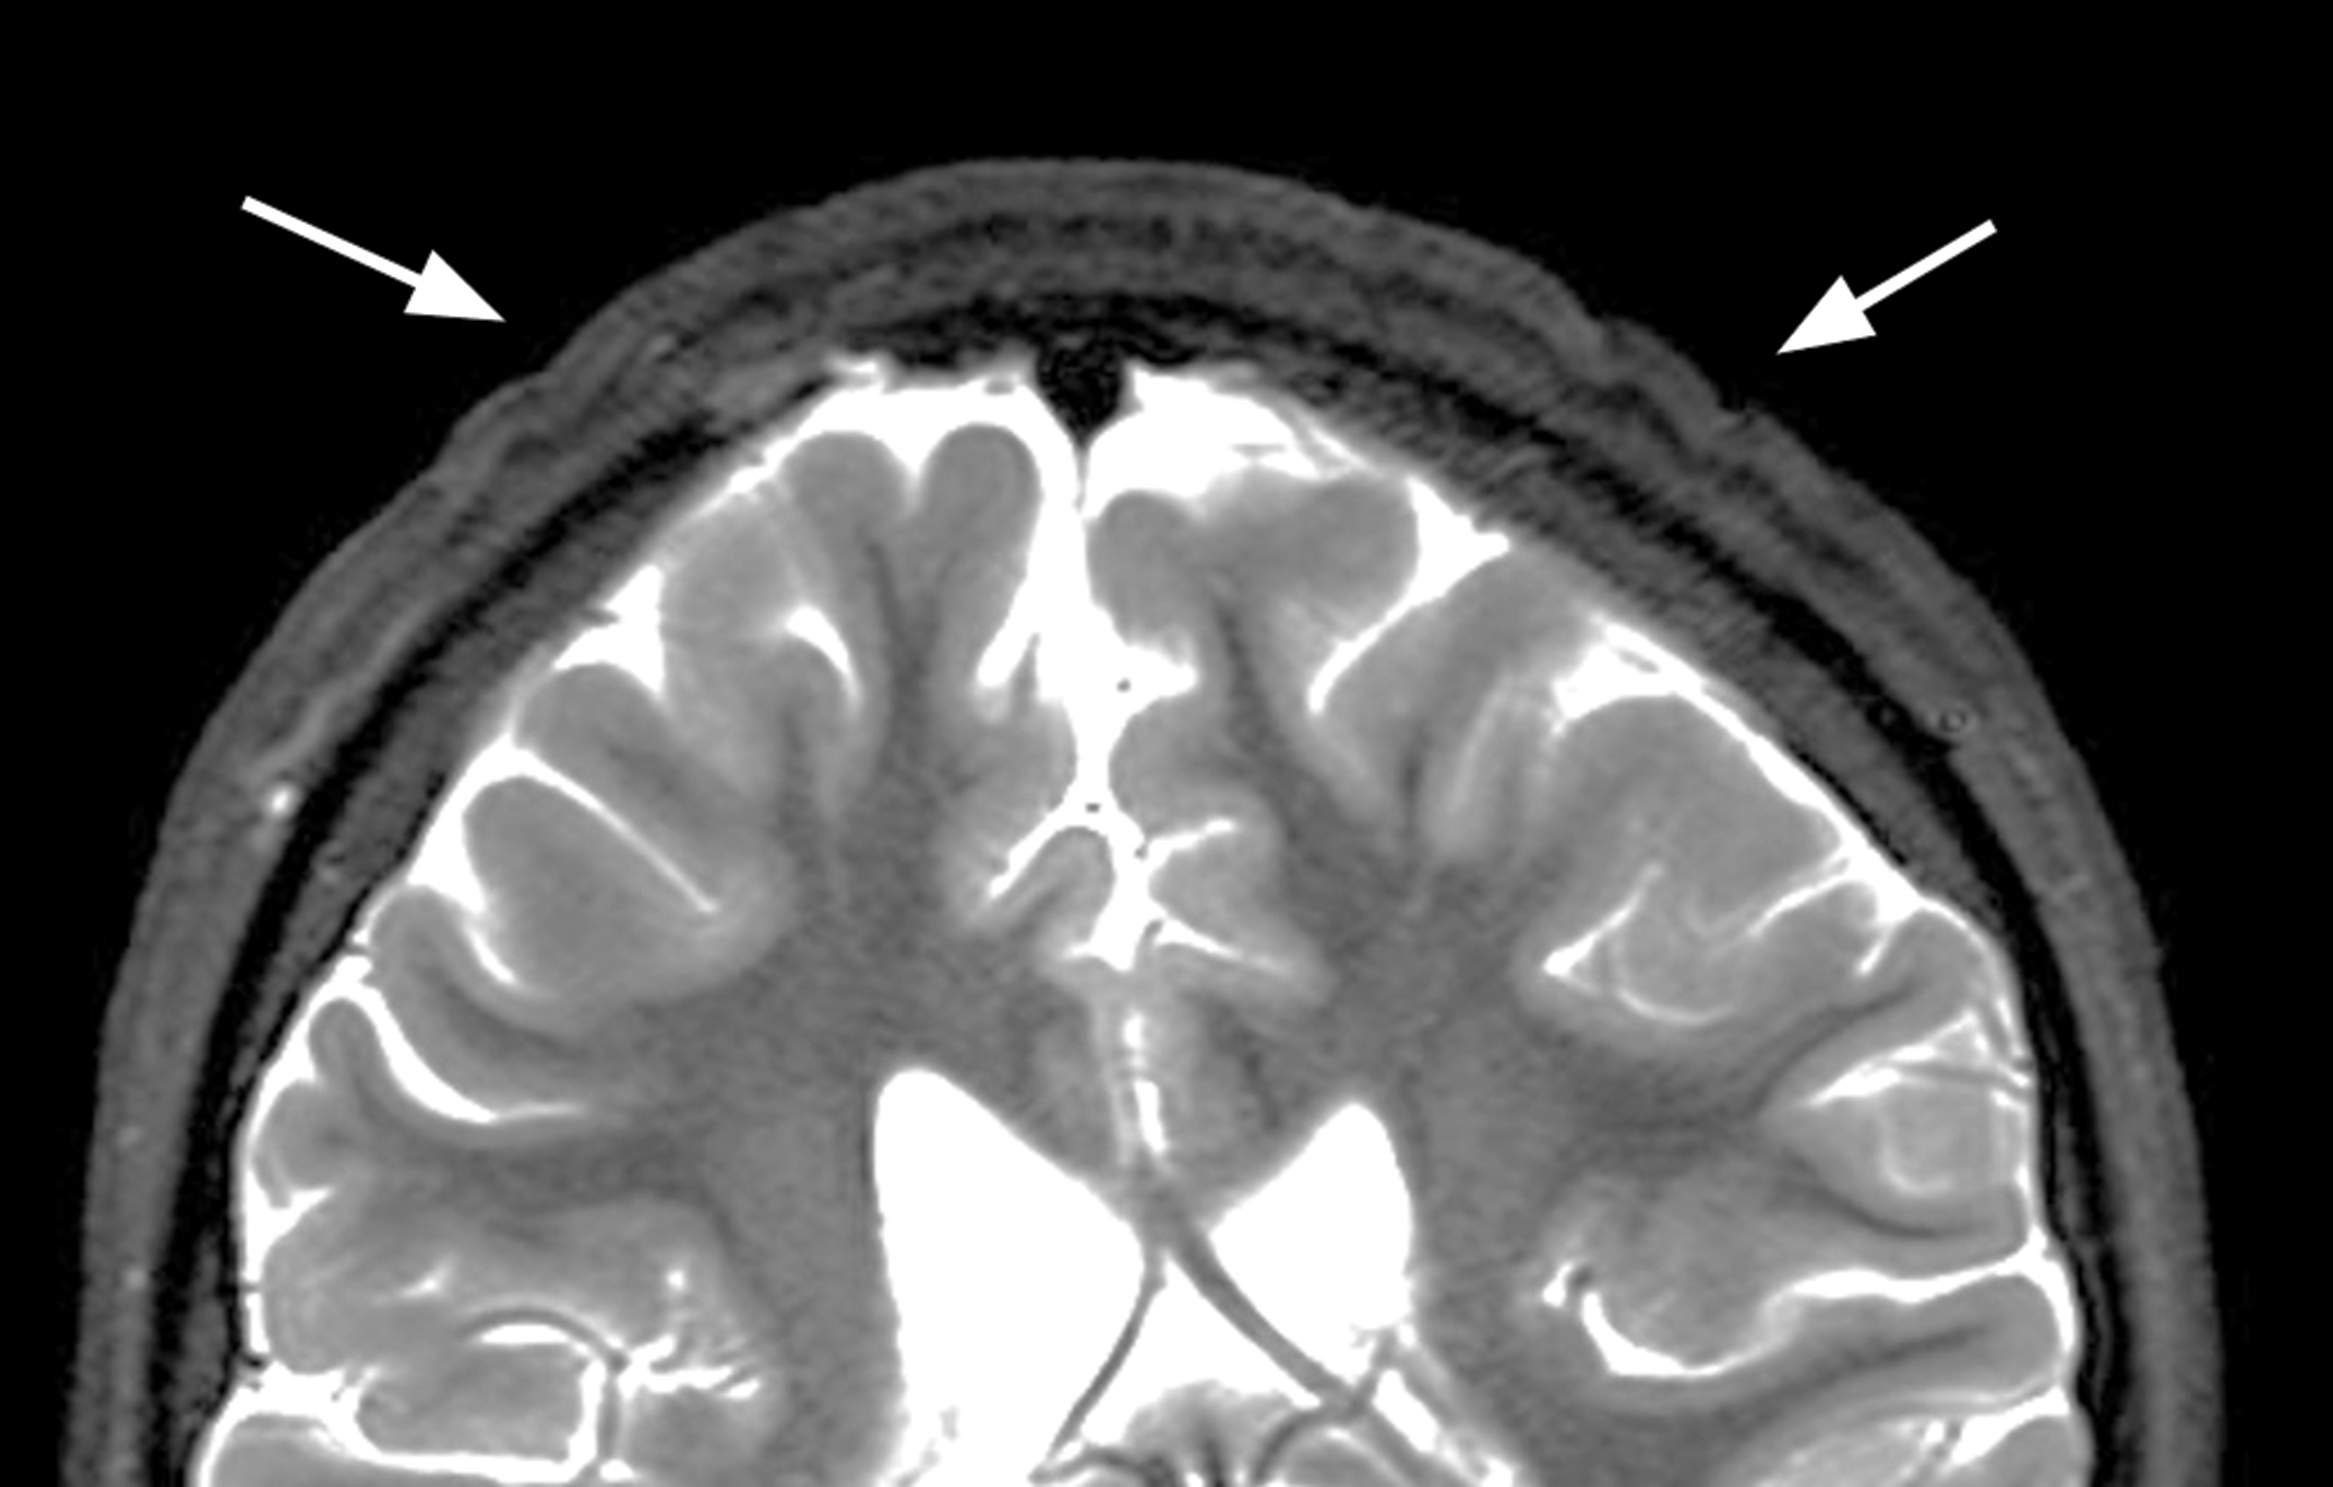

Figure 3

Coronal T2‑weighted image showing decreased thickening of skin folds 4 months after cessation of growth hormone treatment.

Growth hormone therapy was discontinued. Four months later, follow‑up brain MRI showed a decrease in the scalp abnormalities (Figure 3).